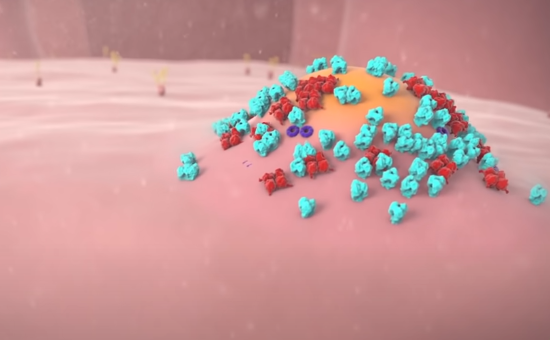

最终,在细胞膜上会聚集大量的病毒蛋白质组件和 RNA。

一个全新装配的新冠状病毒会从细胞工厂被生成出来,他的使命是去感染另一个细胞。至此,这个不幸被病毒控制的细胞会完全沦陷,成为一个制造大量病毒的工厂。直到细胞工厂耗尽所有资源,病毒会果断抛弃它,寻找下一个健康细胞作为感染目标。